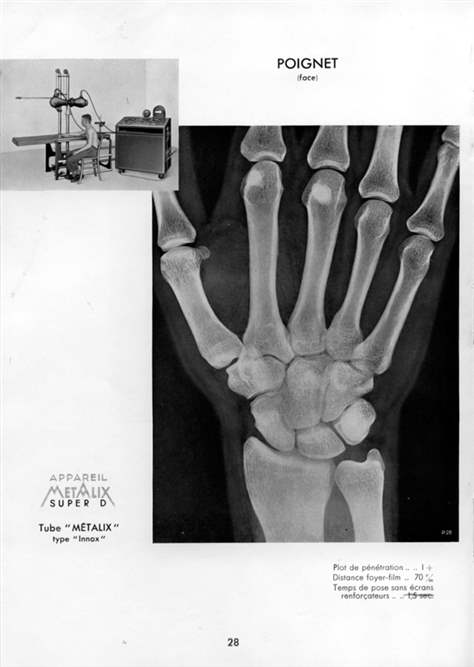

Mandatés par l'Hôpital du Jura bernois, Mémoires d'Ici et le CEJARE (Centre jurassien d'archives et de recherches économiques) ont sélectionné des photographies et des documents illustrant l'évolution des bâtiments hospitaliers de Moutier et Saint-Imier, de leur création à nos jours. Une exposition et son catalogue ont été réalisés et comprennent une soixantaine d'images.